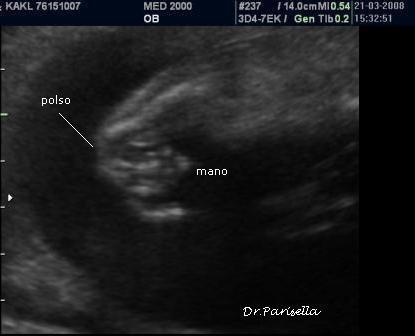

La Diagnosi Prenatale Ecografica si basa su:

1) assenza di movimenti attivi fetali.

2) contratture multiple.